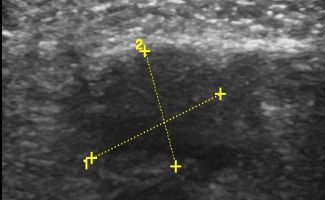

Foot Nerves

- Morton's Neuroma